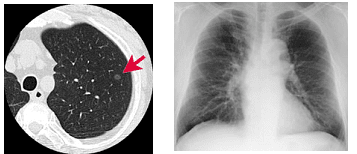

肺炎の画像診断と最新の診療 新型コロナ/富士フイルム、AIで肺炎診断支援 技術開発の詳細情報

新型コロナ/富士フイルム、AIで肺炎診断支援 技術開発。解答・解説】1カ月続く乾性咳嗽を主訴に受診した60歳代女性。肺CT検診 | JR仙台病院。肺がんの診断、特にCTとPET 豊田 尚之 - YouTube。「肺炎の画像診断と最新の診療」藤田次郎定価: ¥ 12,540#藤田次郎 #本 #BOOK #健康 #医学